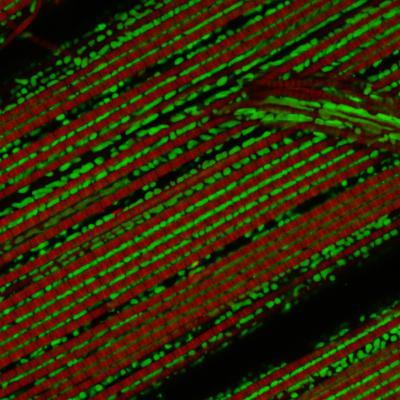

The PINK1 gene plays a role in Parkinson's disease. If the gene is switched off in the fly, the mitochondria (green) are damaged and the animal's muscle fibres (red) disintegrate. The activation of the Ret receptor, which binds the growth factor GNDF in humans, counteracts this degeneration.

(Photo Credit: MPI of Neurobiology / Klein)

The PINK1 gene emerged at a very early stage in evolutionary history and exists in a similar form for example in humans, mice and flies. In the fruit fly Drosophila, a mitochondrial defect triggered by a PINK1 mutation manifests in the fraying of the muscles. Less visible, the flies' neurons also die. The scientists studied the molecular processes involved in these changes and discovered that the activation of the Ret receptor counteracts the muscle degeneration. "This is a really interesting finding which links the mitochondrial degeneration in Parkinson's disease with nerve growth factors," reports RĂ¼diger Klein, the head of the research study. Ret is not an unknown factor for the Martinsried-based neurobiologists: "We already succeeded in demonstrating a few years ago in mice that neurons without the Ret receptor die prematurely and in greater numbers with increasing age," says Klein.